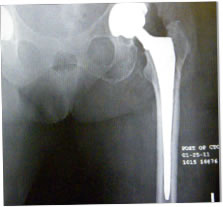

Post-op X-ray

As we have discussed many times slight varus stem positioning does not seem to make a clinical difference with neck stabilized stems.